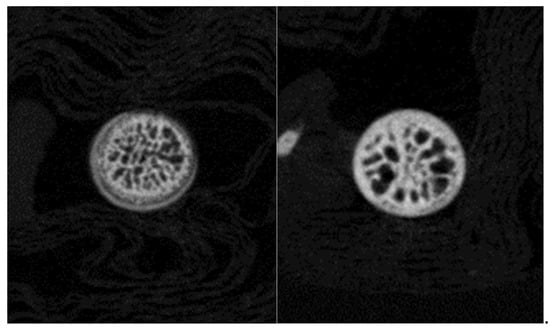

The quality of femur bone, lumbar vertebra, and hip joint of aging mice was evaluated in the present study. Male and female mice of a wide range of ages (7 to 80 weeks), strain Black6, were scanned using X-ray microtomography. Parameters such as mineral density were calculated to assess bone quality.

The parameter values and the images recorded reveal that bony and cartilage tissues remain in healthy condition until the age of 1 year. From this point, decay takes place in bone (osteoporosis) and joints (osteoarthritis). Mineral density of femur and vertebra trabecular bone decreases, while the free space between bone rods increases. The spongy architecture is maintained with wider gaps. The trabecular bone becomes less (Figure 1).

Figure 1.

X-ray microtomographic section of a 7 weeks (left) and 80 weeks (right) lumbar vertebra. Trabecular bone is declining.